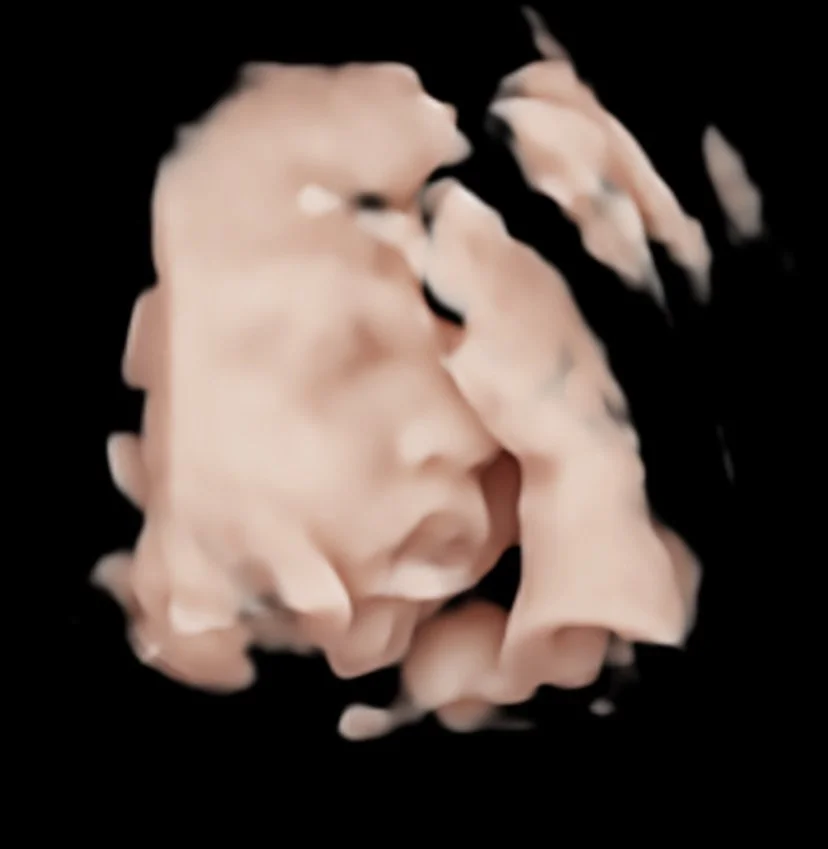

At Body + Bump, we offer 4 different pregnancy ultrasound package types. Please take a moment to view each option in detail. If you have any questions about which appointment type would best suit you, please don’t hesitate to contact us.